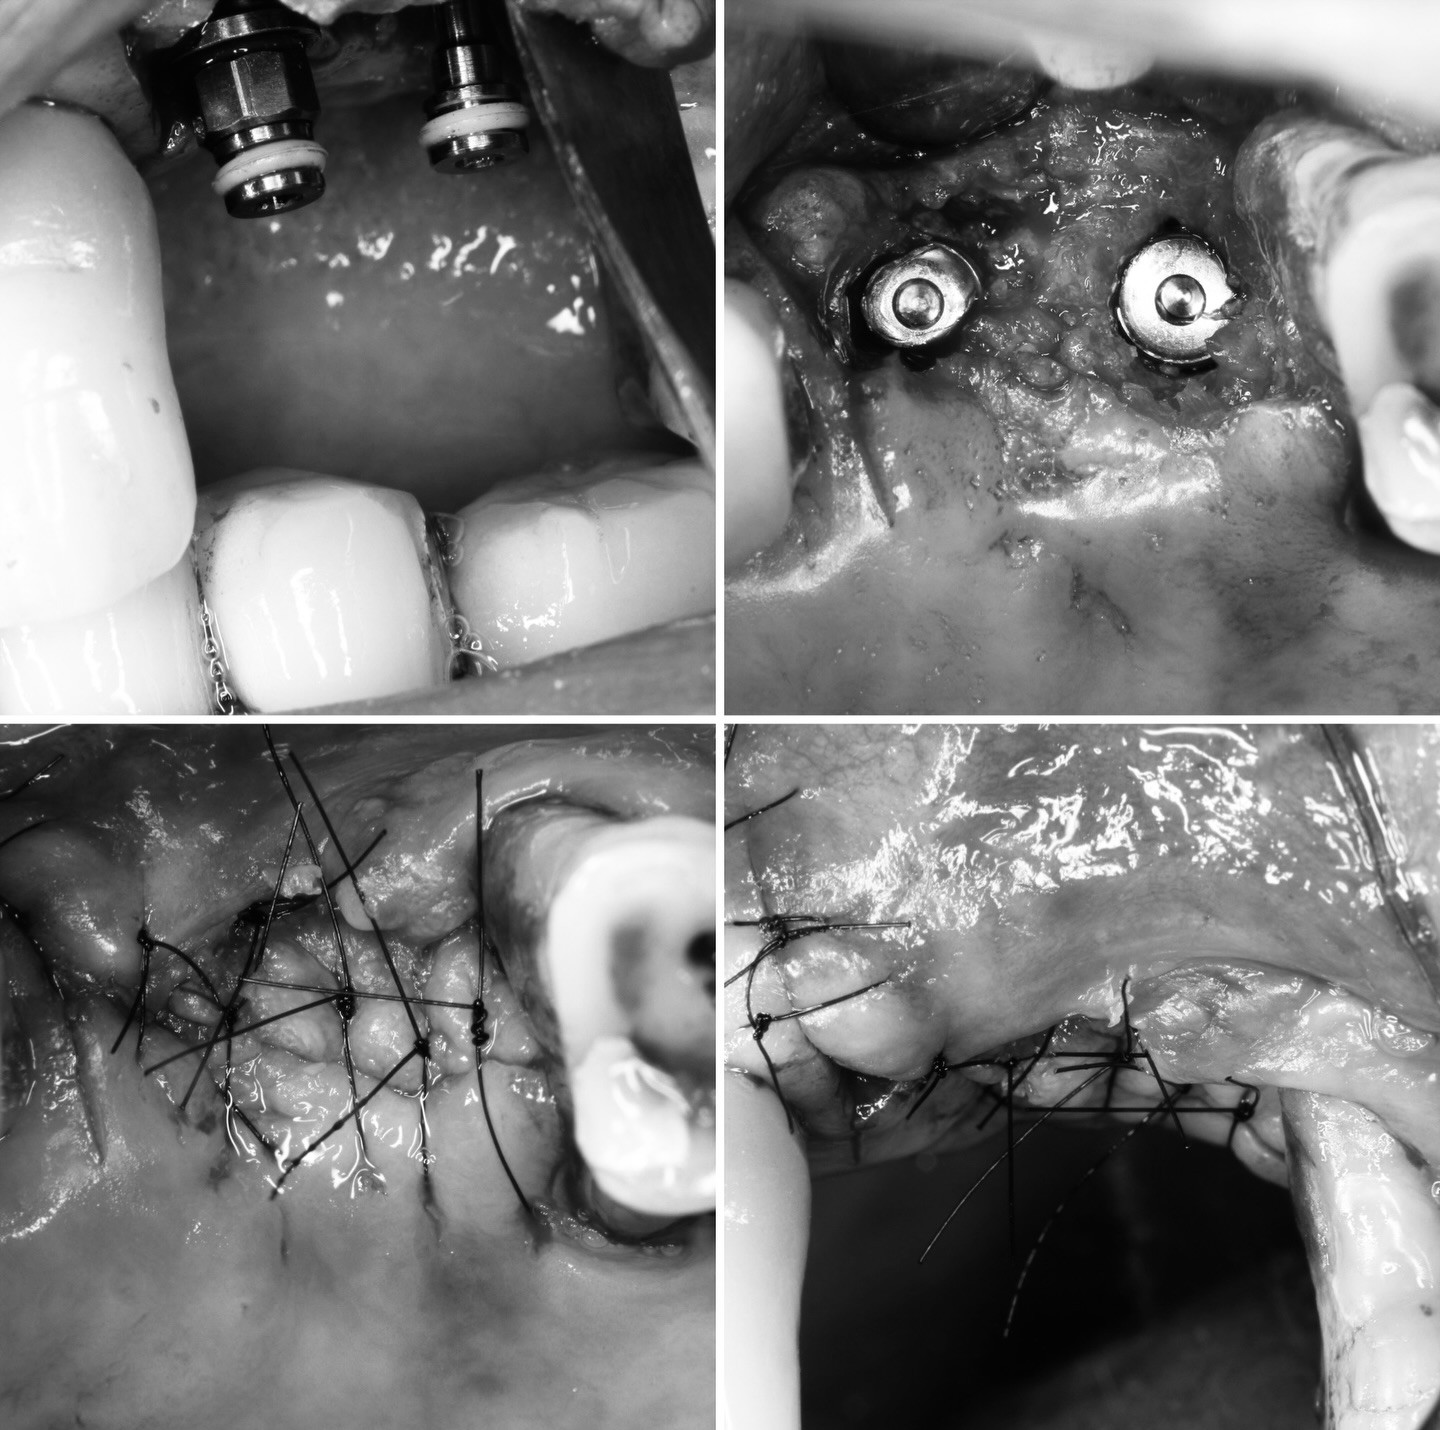

在拔牙的同時,我們一併做了ARP,也就是齒槽骨保存術。在拔牙後填入填入骨粉和覆蓋生物膜,以防止齒槽骨萎縮、以利其生長,為將來植牙創造更好的條件,畢竟要在上面蓋房子,也要打造良好的地基對吧?

在術後的9個月,執行了植牙手術,由於患者本身的自我條件較不足,在手術的同時,還是一起進行了鼻竇增高術:

這也是補骨的一種,解決上顎植牙時因骨頭不足的問題,往上推高鼻竇底部的黏膜,在撐出的空間填入骨粉,以增加骨頭高度和密度,來確保植體有足夠點去支撐,藉此提升植牙成功率,以避免植體穿破鼻竇膜造成鼻竇炎。

今日分享👐我們的患者H小姐,因為左下的小臼齒,中間骨頭缺損非常多,幾乎是中空的狀態了!而舌頰側的部分,是靠左右兩邊的骨頭在支撐;不過也因為有這兩側的骨頭高度撐住空間~所以拔牙後放了骨粉來做填補,使我們的骨頭自然生長、其中也放了骨釘下去,之後如圖做了植牙,後來長出的骨頭也使植牙穩固,可以說是很成功的案例呢☺️☺️

牙根移除後拔牙窩會有空洞,經由拔牙當下放入骨粉及再生膜,減少骨頭流失。

齒槽骨保存術是君悅一直有在做的手術,本篇文章是整理出六月簡院長做的三台手術的X光片,可以看出牙齒拔掉後放入骨粉的樣態,數個月後(通常等半年),這些骨粉會漸漸被自己骨頭取代,在片子上就不會看出骨粉與拔牙窩壁壘分明的樣子。院長想提醒醫師們,須留意舌側皮瓣,因舌側骨頭通常較多,在撥鬆皮瓣有時會造成皮瓣的破裂,建議慢撥控制力量並貼著骨壁走。院長也認為即拔即種對患者有省時少手術的優勢,若條件許可應該要跟患者建議。